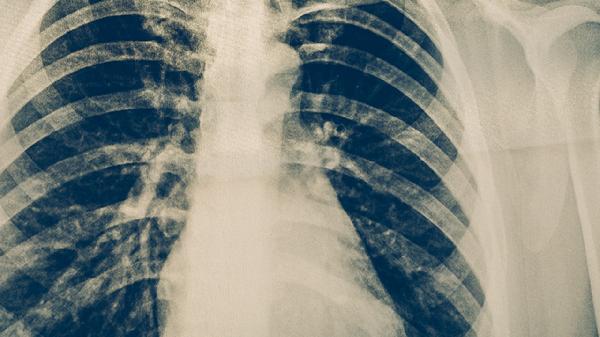

肺癌病人可通过调整饮食、适度运动、心理疏导、定期复查、避免危险因素等方式进行保健。肺癌可能与吸烟、空气污染、职业暴露、遗传等因素有关,通常表现为咳嗽、胸痛、咯血等症状。